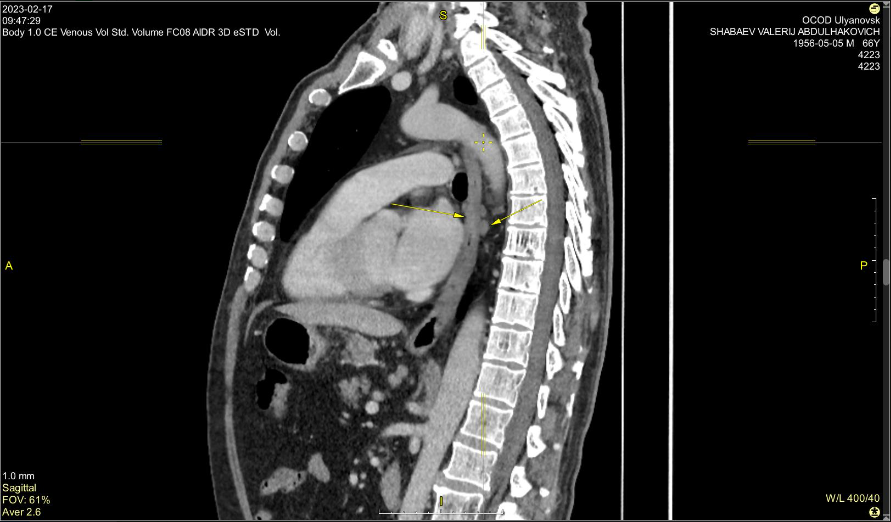

Материал и методы. Представлено 3 клинических случая одновременного развития плоскоклеточного рака пищевода и аденокарциномы желудка у пациентов, получавших лечение в ГУЗ «Областной клинический онкологический диспансер», г. Ульяновск, и ГАУЗ СО «Свердловский областной онкологический диспансер», г. Екатеринбург. Пациентам проведены хирургическое вмешательство, химиотерапия и лучевая терапия.

Результаты. Первично-множественный синхронный плоскоклеточный рак пищевода и аденокарцинома желудка представляют собой сложную клиническую задачу, требующую вмешательства мультидисциплинарной команды специалистов. Химиолучевая терапия с использованием схемы FOLFOX продемонстрировала хорошую переносимость и позволила достичь удовлетворительного клинического ответа со стороны опухолей обеих локализаций.